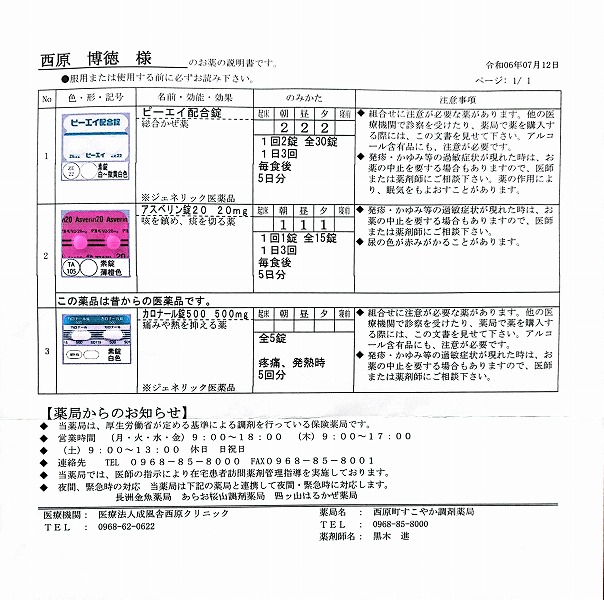

2024.7.12(金) 2回目のコロナ感染 7.16(火)検査で陽性

2024.4.13 オロパタジンに戻る

2024.3.9 鼻炎と目のかゆみがひどく、オロパタジン⇒デザレックス&点眼薬 アレジオン に変更 2.10 血液検査結果